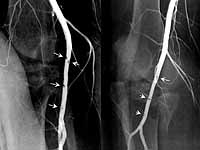

Here is an example of an asymptomatic  minimal injury (a mural hematoma, not intimal flap) that did require operative therapy.

This young man in his 20's sustained a shotgun wound to the thigh. Arteriography shows a mural hematoma. The five Ps were intact. He returned  almost one year later, with a healed shotgun wound with a nonhealing heel ulcer resulting from the stricture of the SFA at the site of the intramural hematoma. Bypass was performed. Ulcer healed.

This asymptomatic patient with a gunshot wound of the knee had arteriography which showed a bulge and an intimal flap. A followup several days later showed expansion of either a pseudoaneurysm or a false aneurysm. The distally based flap is more prominent. We treated this with a stent graft. One year ultrasound followup showed patency of the stent graft.

Would this injury have healed spontaneously? I don't know. I would conjecture that it would not. Why did this asymptomatic patient expand the bulge? Was it the distally based flap, or was it the underlying pathology of the wall? Conjecture.

This asymptomatic patient with a gunshot wound of the knee had arteriography which showd a bulge and an intimal flap. A followup several days later showed expansion of either a pseudoaneurysm or a false aneurysm. The distally based flap is more prominent. We treated this with a stent graft. One year ultrasound followup showed patency of the stent graft.